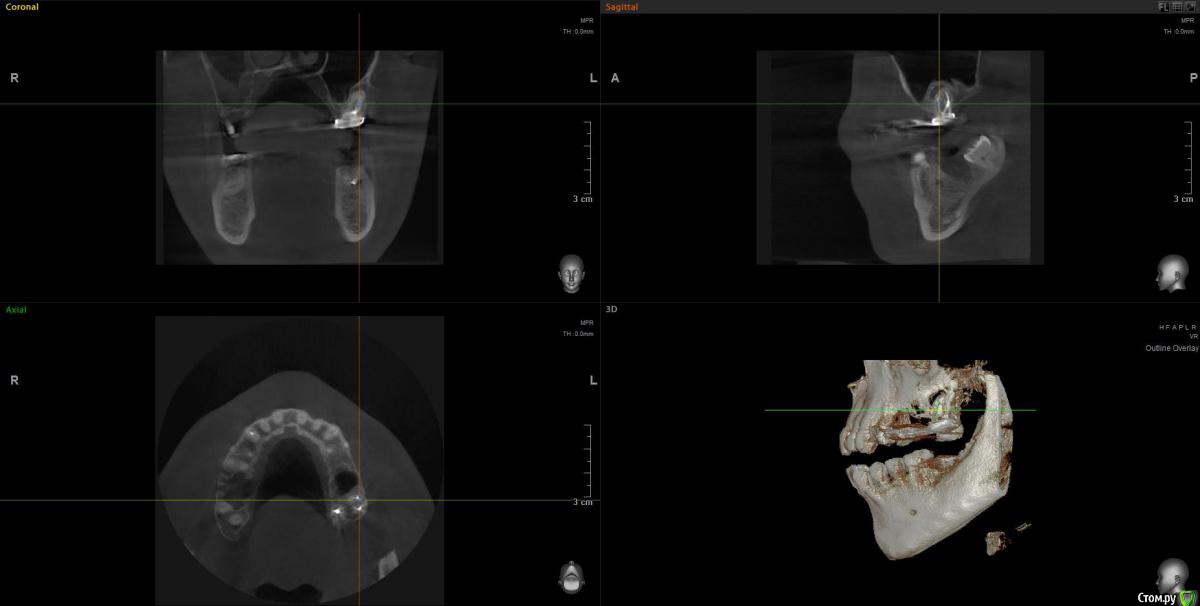

Ботинок Опубликовано 25 июля, 2020 Поделиться Опубликовано 25 июля, 2020 (изменено) Здравствуйте, Спасибо за ваше время для просмотра моей КТ. Речь про 27ой зуб https://drive.google.com/file/d/1yeLfeXNm_Ex4w3dMc1R1VGEqdMZLexYT/view?usp=sharing Жду ответов Изменено 25 июля, 2020 пользователем Ботинок Ссылка на комментарий